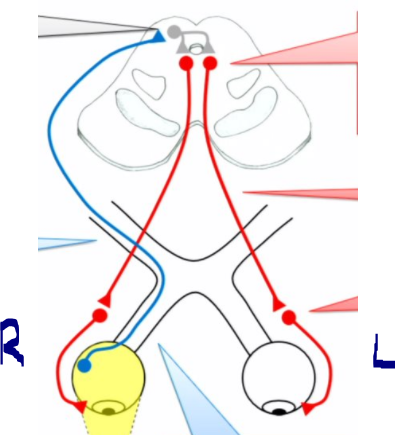

describe the pupillary light reflex circuitry

• shining light into the right eye activates retinal ganglion cells

• the axons of retinal gang. cells form the afferent limb of the reflex arc

• about 50% of the fibers forming the optic nerve stay ipsilateral and continue in the optic tract of the same side, while the other 50% gang. cell axons cross at the optic chiasm and then run along the contralateral optic tract

• not all fibers carrying visual info. synpase in the LGN; some fibers synapse in the pretectal nucleus of the midbrain

• collaterals of axons originating in the pretectal nucleus bilaterally innervate the EW nuclei, which are the accessory nuclei of CN III